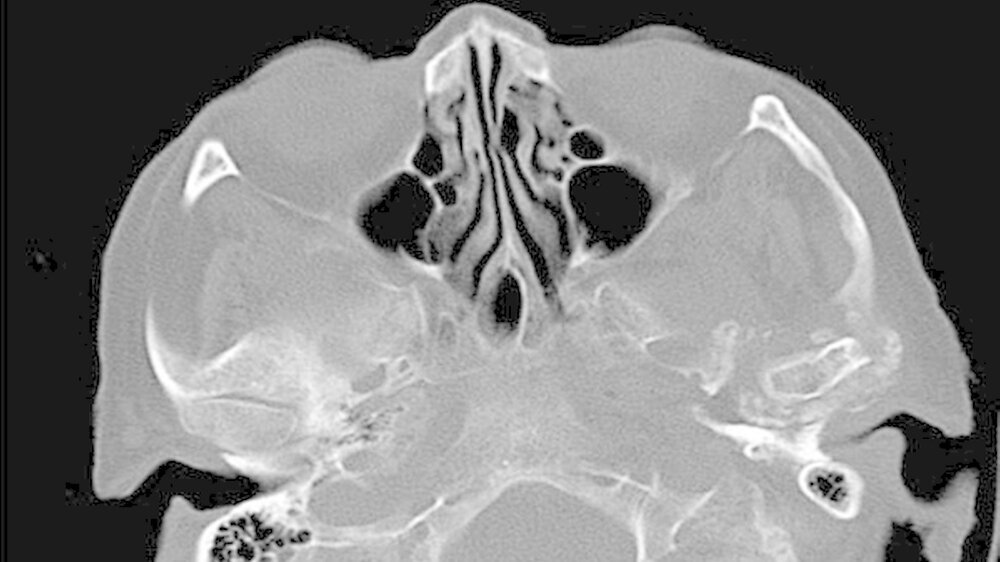

Es war lediglich ein stark verschmälerter Gelenkspalt im Bereich des linken Kiefergelenks erkennbar, woraufhin eine Computertomografie des Unterkiefers durchgeführt wurde (Abbildungen 1 und 2). Dabei zeigten sich eine Deformierung des linken Kiefergelenksköpfchens mit Unregelmäßigkeiten der Kortikalis sowie eine Fremdkörpereinlagerung (freie Gelenkkörperchen) im Bereich des Gelenkspalts (Abbildungen 3 und 4).